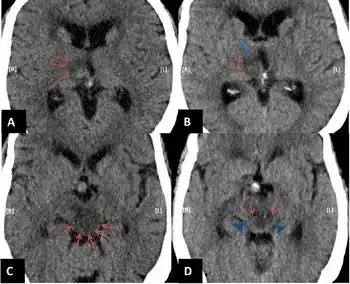

{{cite book}}: CS1 maint: others (link) - ↑ Hedna, Vishnumurthy Shushrutha; Bidari, Sharathchandra; Gubernick, David; Ansari, Saeed; Satriotomo, Irawan; Khan, Asif A.; Qureshi, Adnan I. (18 November 2014). "Treatment of stroke related refractory brain edema using mixed vasopressin antagonism: a case report and review of the literature". BMC neurology. 14: 213. doi:10.1186/s12883-014-0213-0. ISSN 1471-2377. Retrieved 28 February 2024.